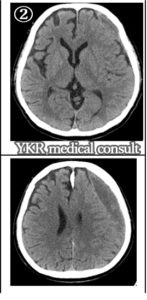

②事故後約10か月:この時点でも左側において血腫は比較的多めに残存している。